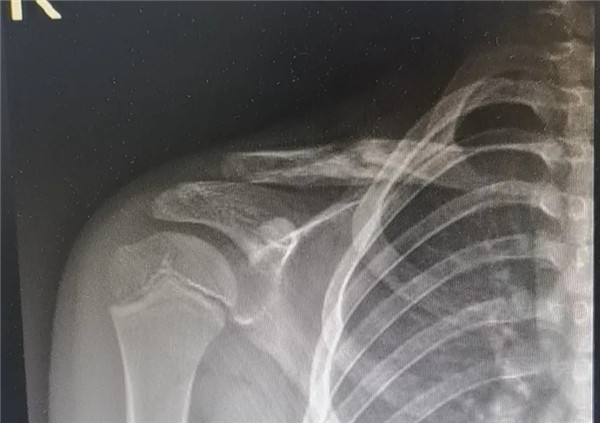

6月3日,在征得家屬同意,洋洋的身體符合手術(shù)指征后,洋洋接受了右鎖骨骨折切開復(fù)位內(nèi)固定術(shù),手術(shù)由應(yīng)文世主任主刀。術(shù)中可見右鎖骨呈粉碎性骨折,骨折端移位明顯。一個(gè)小時(shí)后,手術(shù)順利結(jié)束。術(shù)后,洋洋恢復(fù)良好,6月9日順利出院。一個(gè)月后,在來復(fù)查時(shí),洋洋的媽媽帶來了一面錦旗送予應(yīng)文世主任及手外科周小君副主任,以感謝他們的高超技術(shù)及優(yōu)質(zhì)服務(wù)。

復(fù)位后